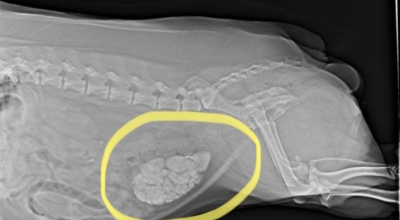

요로결석이란

수분 섭취 감소는 요로결석의 가장 중요한 발병 이유가 되는 것 이라고 합니다. 수분의 섭취가 떨어지면 요석결정이 소변에 머무르는 시간이 길어져 요석형성이 증가하게 되며 요로결석의 발생은 유전적인 소인이 있다는 것이 정설이나 후천적인 생활습관도 관련성을 보입니다.

요로결석의 치료방법은 당연히 결석을 없애는 방법이 최우선인데요 체외충격파 쇄석술 이라고 하는 시술을 통해 결석을 자연 배출될 수 있도록 하는 방법이 있습니다. 충격파 장치에서 고에너지 충격파를 쬐어 결석을 파괴하면, 결석 조각이 알아서 배출될 수 있도록 하는 시술입니다.